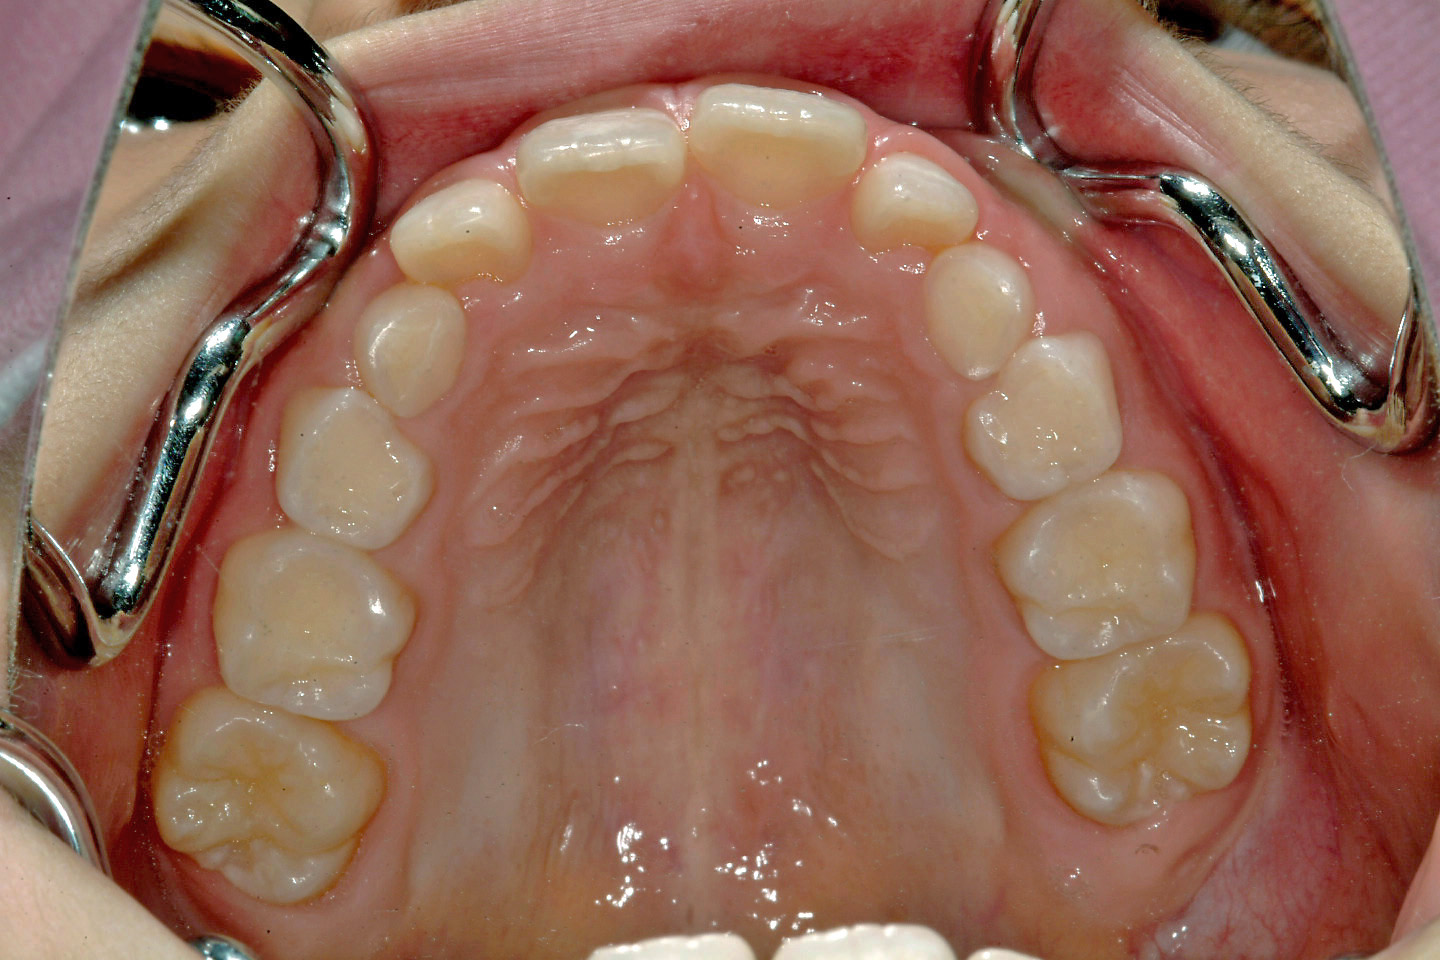

過蓋咬合(深いかみ合わせ)

叢生(乱ぐい歯)

上顎前突(出っ歯)

出っ歯を気にされて来院された9歳の女子です。下顎の後退により下顎前歯が見えないかみ合わせでした。前期治療として上顎骨の成長抑制のためのヘッドギアーと併用する形で咬合斜面板による下顎の前方誘導を行いました。その後、非抜歯によるエッジワイズ治療に移行いたしました。前期治療に約3年、後期治療に約2年を要しております。